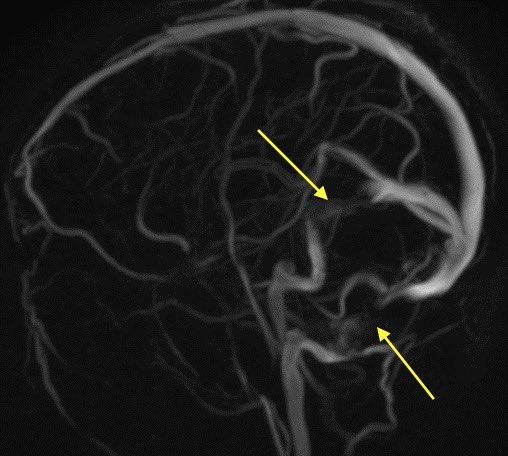

4️⃣Transverse/sigmoid sinus junction stenosis: stenosis may lead to the IIH or the increased pressure may lead to extrinsic compression of the sinuses, which comes first is unknown

Classically, this occurs at the junctions of transverse and sigmoid sinuses or lateral transverse

Here is an example of an intracranial venogram pre and post stenting of the b/l Transverse/sigmoid sinus junctions